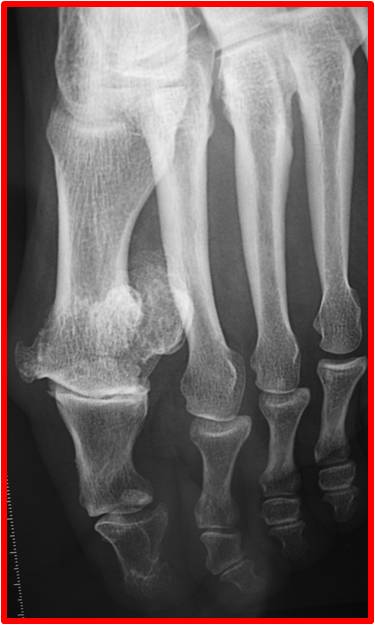

La radiologie

Elle confirme l’arthrose.